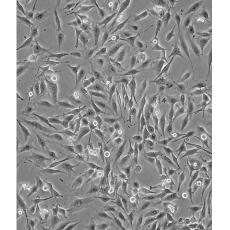

形態特征 spindle shaped

細胞描述 MDA-MB-435S是一種紡錘形的細胞,1976年由其親本(435)中篩選得到。435是從31歲的轉移性乳腺導管腺癌女性患者胸水中分離得到。當用熒光染料對微管蛋白進行染色時親本細胞顯現散布特征(II型)。最近通過cDNA陣列研究表明,親本(MDA-MB-435)可歸入黑素瘤起源。